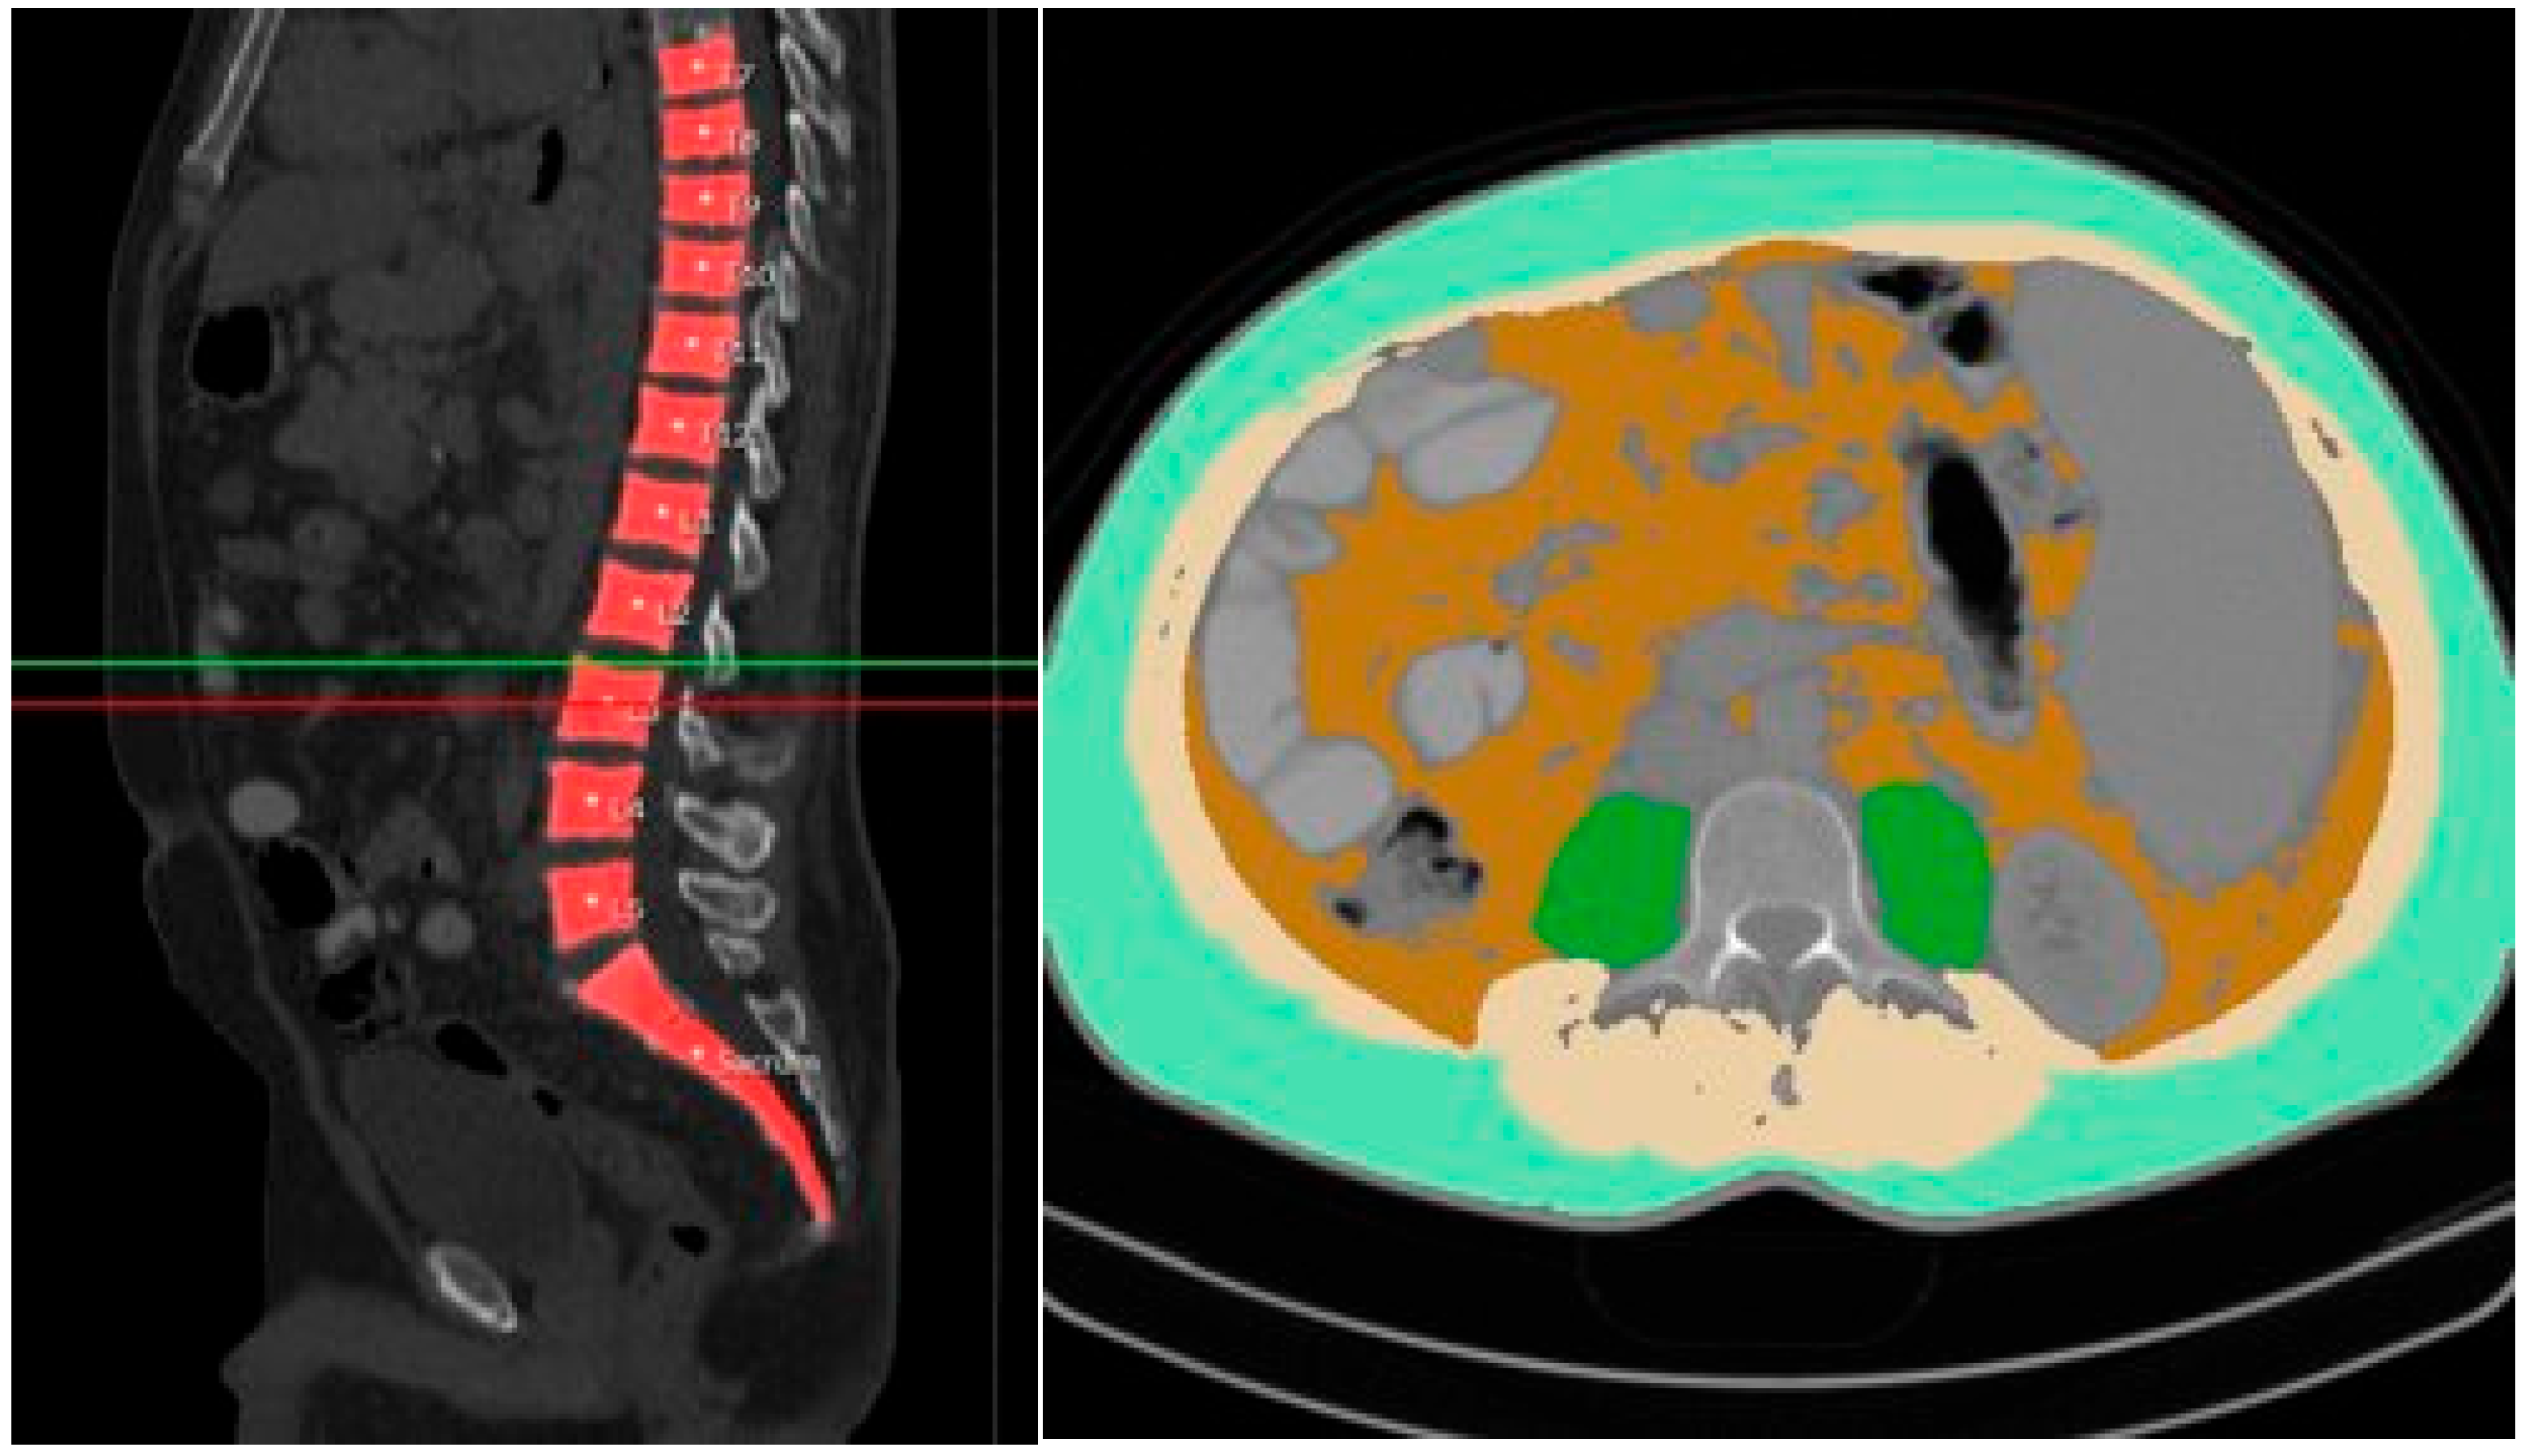

| LSMI | Lumbar skeletal muscle index |

| PACS | Picture archiving and communication system |

| PMA | Psoas muscle area |

| SMI | Skeletal muscle index |